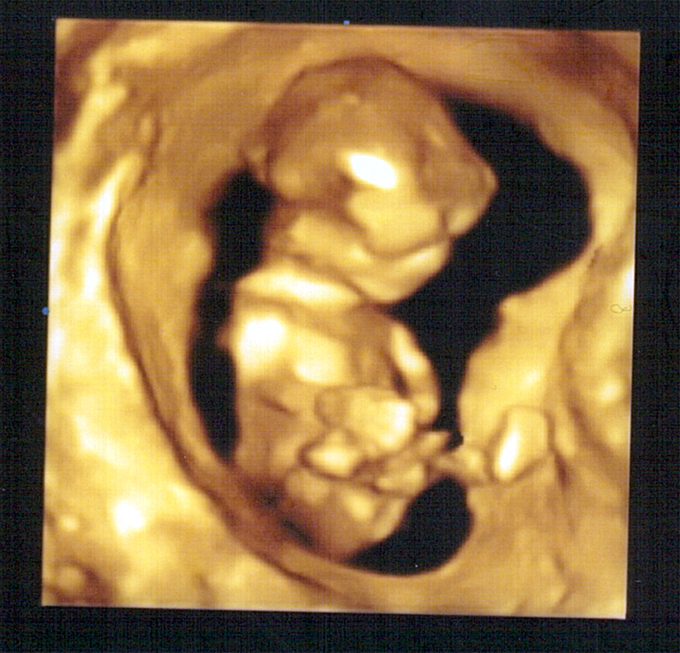

강이 3차원 사진 ^^ (10.12.24)

우리 강이 입체 사진 찍고 왔어요 ㅎㅎ..